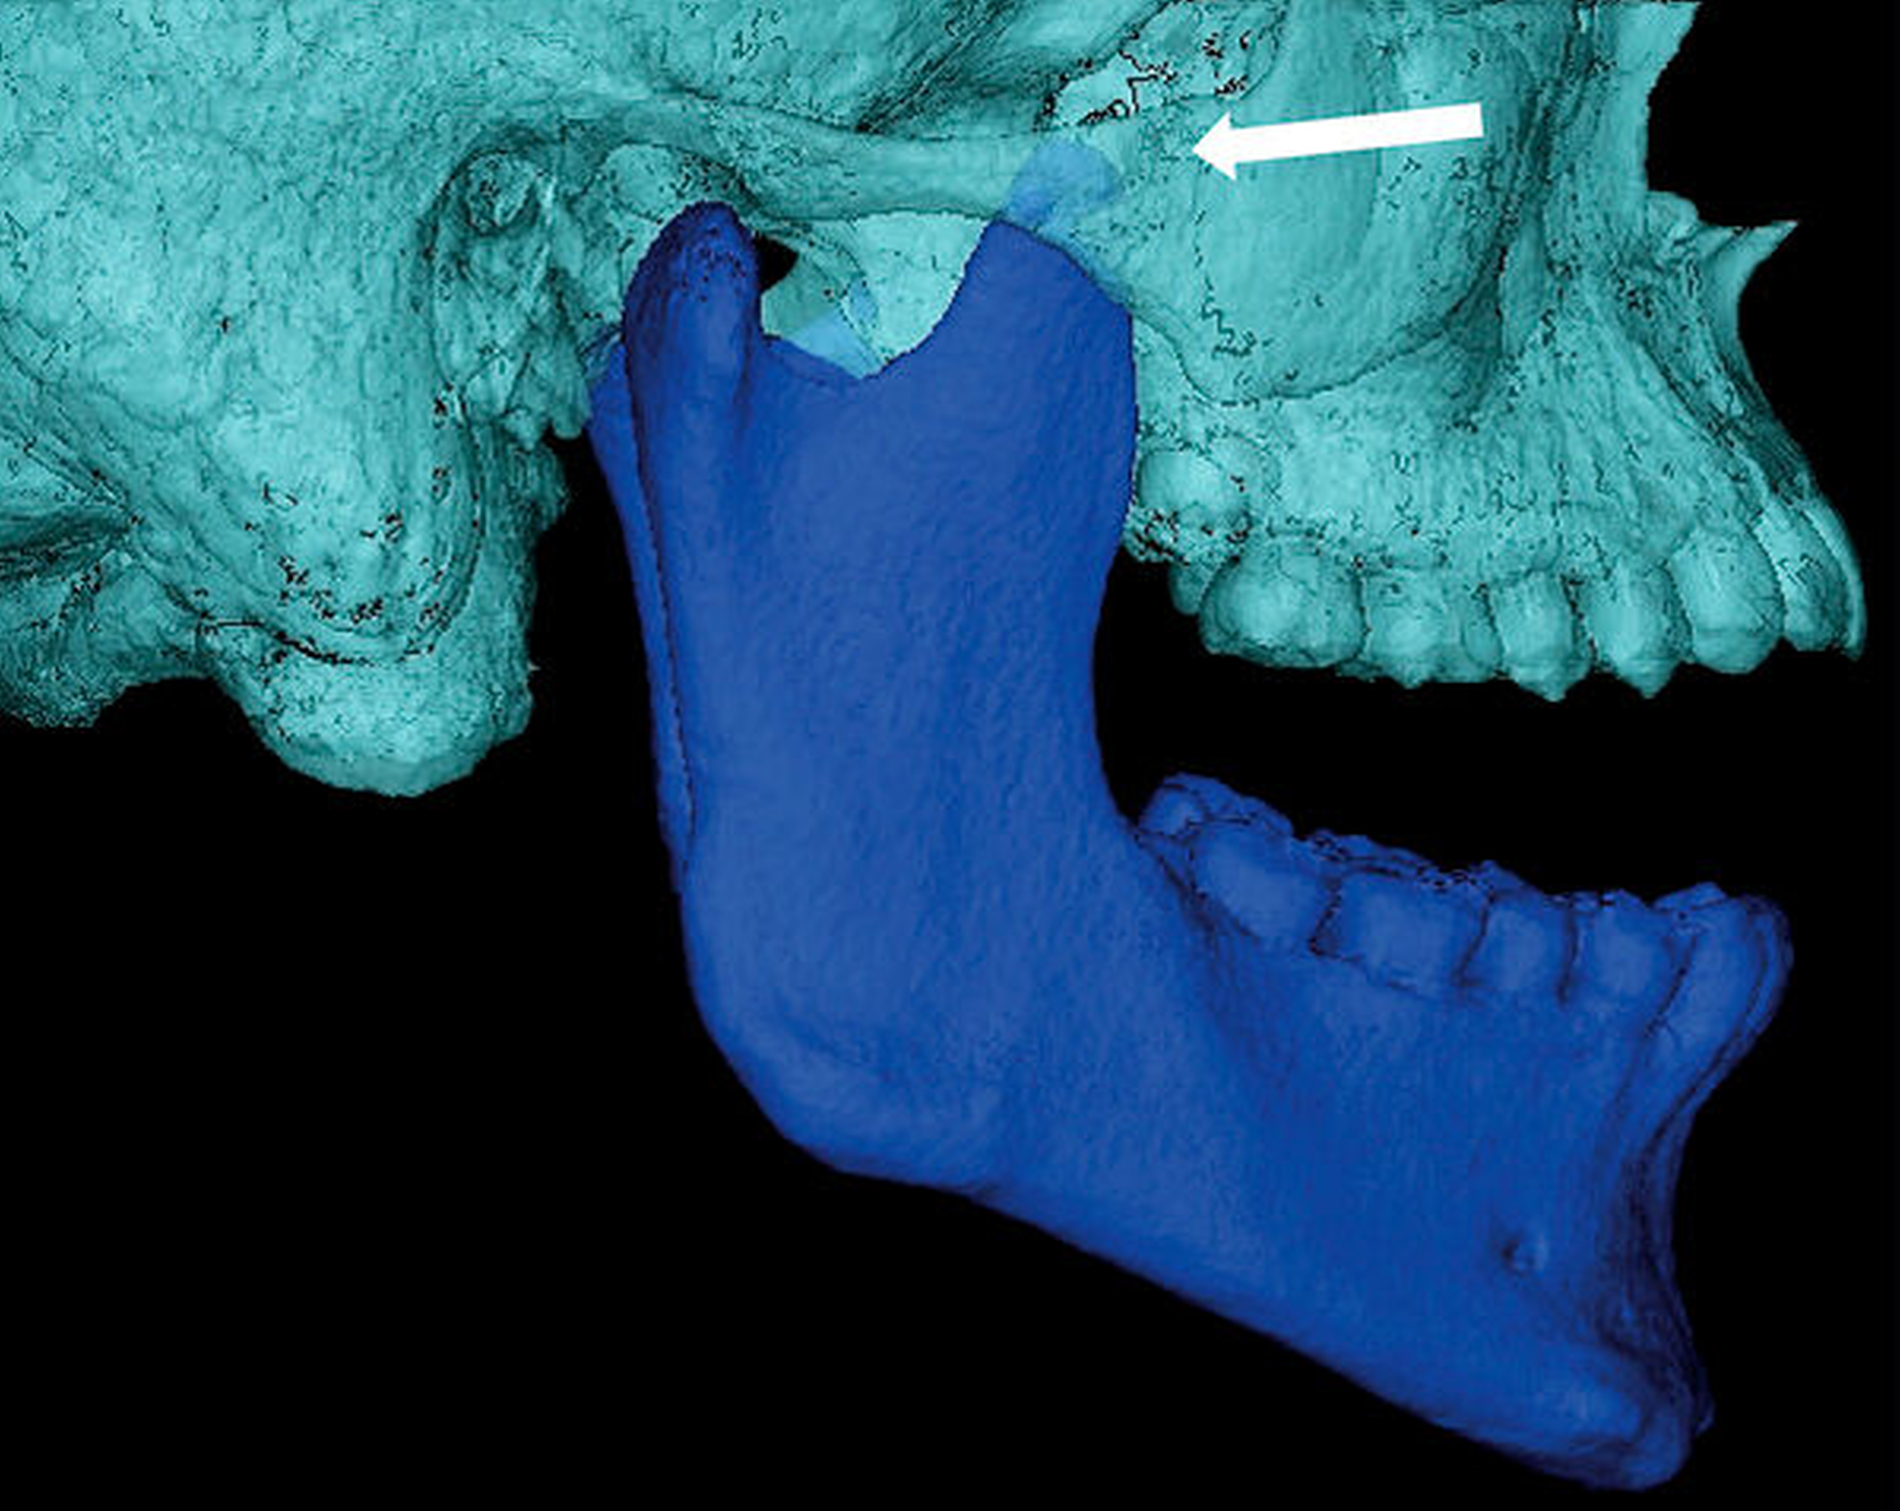

Präoperativ führten wir zur exakten Eingriffsplanung eine Computertomografie durch. Hier zeigte sich erneut die ausgeprägte Verlängerung der Fortsätze (Abbildung 5). Intraoperativ konnte beim Patienten nach beidseitiger Resektion bereits eine SKD von 44 mm erreicht werden (Abbildung 6). Die Weisheitszahnentfernung erfolgte nun problemlos. Das postoperativ angefertigte OPG zeigt die Resektionsflächen beidseits (Abbildung 7).